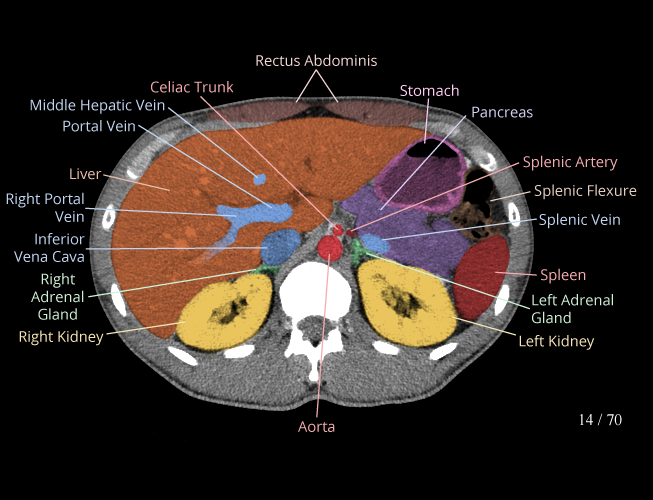

Body

Covers abdominal CT anatomy.